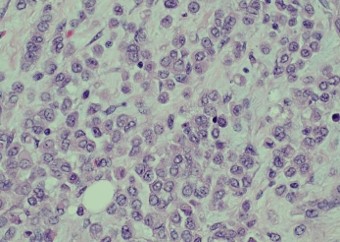

Pathology of the right hemicolectomy specimen was “involvement by metastatic carcinoma, immunoprofile compatible with breast primary”. The cytokeratin profile was CK7+, GATA3+ and MOC-31+, and negative for CK20 and CDX-2. There was very focal positivity for E-cadherin, while p120 catenin mostly showed cytoplasmic staining in the tumour cells. Microscopic examination suggested that the tumour invaded from mucosal side of the intestinal towards the serosa; the proximal and distal resection margins were clear. The morphology and immunoprofile point towards a metastatic carcinoma of breast.